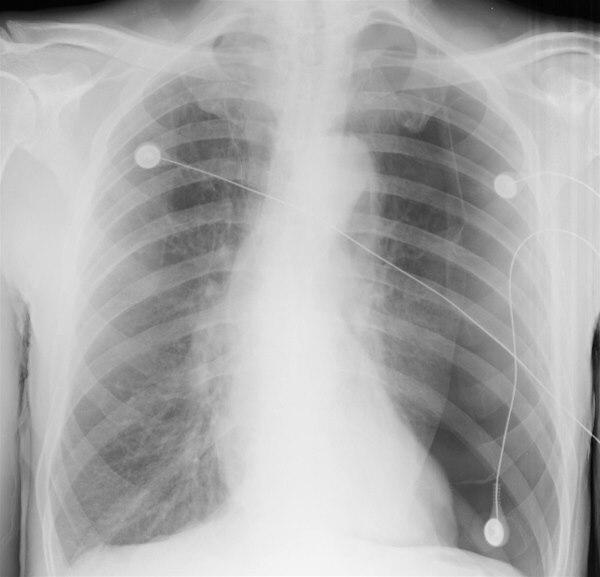

Røntgenbildet viser en venstresidig pneumothorax der lungen er redusert til ca. halve volumet. Ytterkanten på venstre lunge er klart synlig, og hjertet er forskjøvet over mot høyre side.